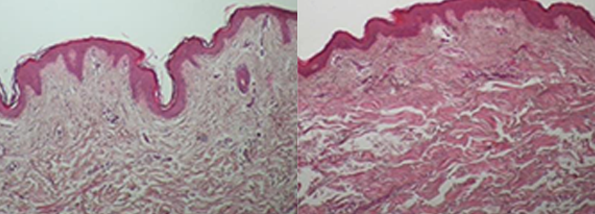

Onda Effects

• Collagen Remodeling

Immediate skin tightening and contouring effects

• Collagen Activation

Targeted treatment of collagen and fat cells without epidermal damage